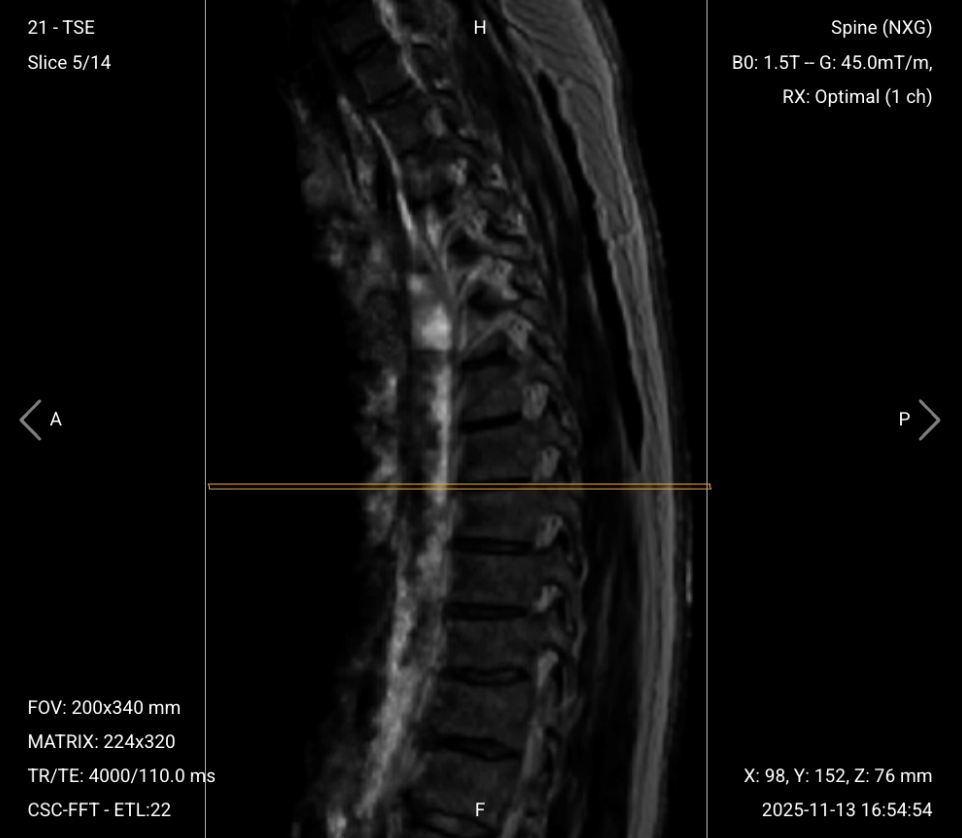

Parameters for Sagittal T2 TSE:

| Field-of-View (FOV) | 200 × 340 mm | Rectangular FOV optimized for the thoracic spine's vertical extent, covering superior-to-inferior while minimizing anterior-posterior to reduce scan time. |

| Matrix | 224 × 320 | Medium matrix size provides sufficient resolution while maintaining short scan time and high SNR. |

| Foldover Direction (Phase) | Foot-to-Head (FH) / Superior-to-Inferior | Aligns with cerebrospinal fluid flow to reduce flow artifacts. |

| Number of Slices | 14–18 | Enough slices to cover the thoracic spine from right to left. |

| Slice Thickness | 4 mm | Medium thickness provides good resolution without sacrificing scan time or SNR. |

| Slice Gap | 0.4 mm | 10% of slice thickness prevents crosstalk while ensuring continuity. |

| NEX / Averages | 1–2 | Provides enough SNR while keeping scan time short. |

| Turbo Factor / ETL | 16–24 | Higher turbo factor enhances T2 contrast and reduces scan time. |

| Bandwidth | 50,000 Hz | Medium bandwidth balances SNR with chemical shift artifact reduction. Lower than typical values to improve SNR in the challenging thoracic region. |

| Fold-over Suppression | Yes | Prevents aliasing or wrap-around artifacts. |

✅ Sagittal T2 TSE of Thoracic Spine – Correct Image Example:

Things to Look for in Sagittal T2: